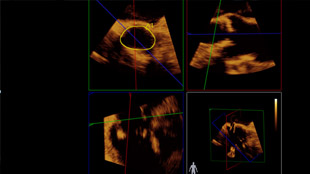

تم تشخيص أحد المرضى لديك بتضيّق في الصمام الأورطي المصحوب بأعراض. يبلغ عمر المريضة 85 عامًا وهي تعاني من السكري وارتفاع ضغط الدم. أنت تدرك خطورة وضعها الصحي ما يجعلها غير مناسبة لجراحة القلب ولكن يسمح لها بأن تكون مرشحة لاستبدال الصمام الأورطي باستخدام القسطرة (TAVR). في يومنا هذا، تمنح حلول التصوير المبتكرة والأجهزة التي تعمل عن طريق الجلد الأمل لبعض المرضى الذين لا تتوفر لهم حتى الآن أي خيارات علاجية أخرى.